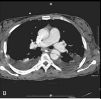

This amount of blood immediately drained from a chest tube, or this hourly rate (ml/hr) of ongoing bleeding, indicates the need for surgical thoracotomy.

What is What is >1,500 mL immediately or >200 mL/hr ongoing output?

This blunt chest injury often presents with hypoxia out of proportion to chest X-ray findings and is managed primarily with supportive care and oxygenation.

What are pulmonary contusions?